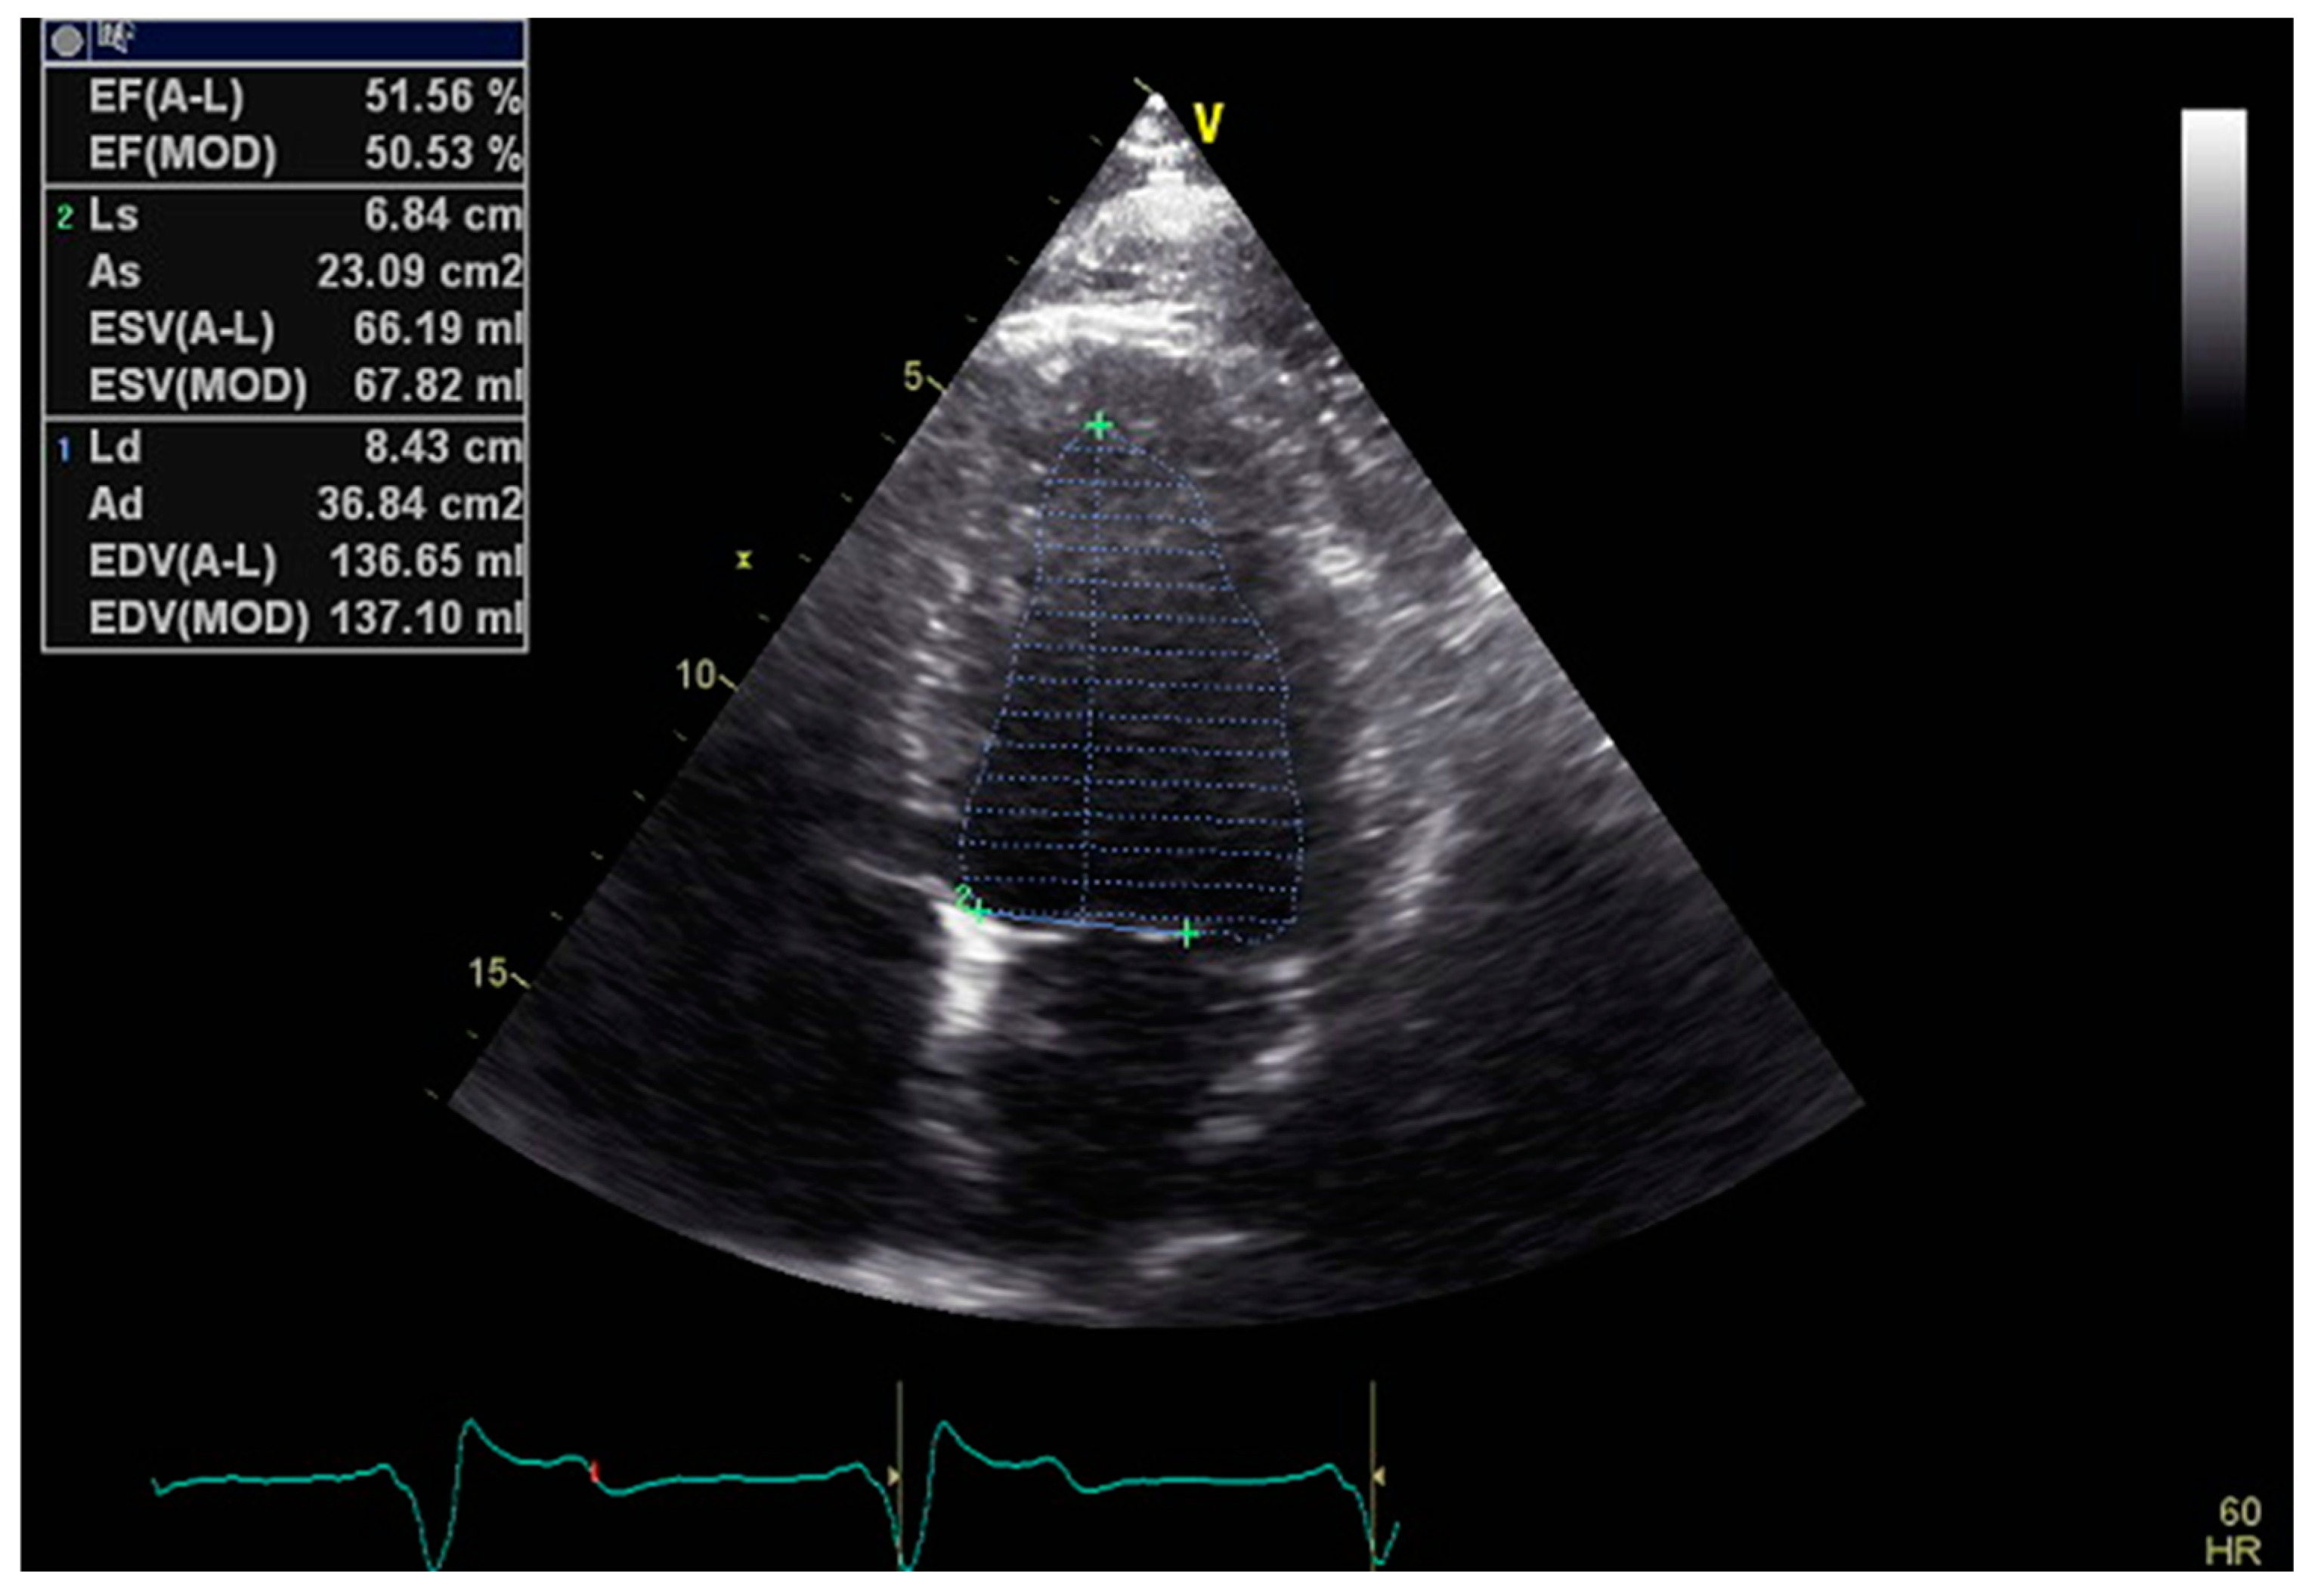

Mitral Annular Plane Systolic Excursion (MAPSE): A Review of a Simple and Forgotten Parameter for Assessing Left Ventricle Function